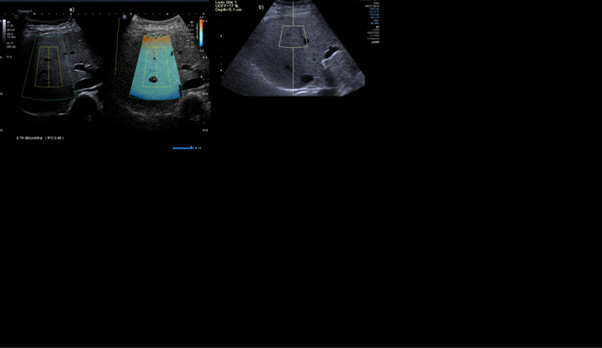

Analysis of Outliers

The outliers with the largest absolute differences (two or more grades) were primarily patients with the highest BMIs (>32), highest SCD (>3.2), or both, with S3 graded as S1 by Aplio (Figures 9,10). There were two outlier cases with SCD >2.5 and BMI <30, where fat grades S2,3 on sequoia were graded as S0 and S1 by Aplio (Figure 9). The latter cases indicate measurement inconsistencies owing to high SCD patient characteristics that affect agreement. The correlation MRI of the other outlier patients revealed high liver ferritin levels, which was a confounding factor leading to a systematic bias (Figure 10). We also analyzed 38 cases with discrepant grades of inflammation and fibrosis as confounding factors for discrepancies in steatosis grades. The mean SWD in cases without grade discrepancy were 15.07 while SWD grade discrepancy and 13.81%, respectively. The t-test p-value (0.233) indicates no statistically significant difference in SWD between discrepancy and non-discrepancy groups (Figure 11).